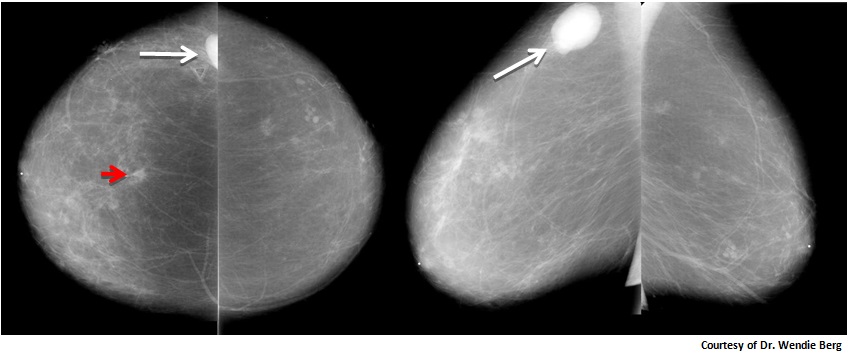

Феномен гипердиагностики в маммографии: примеры и иллюстрации

Раздел: Образы вокруг